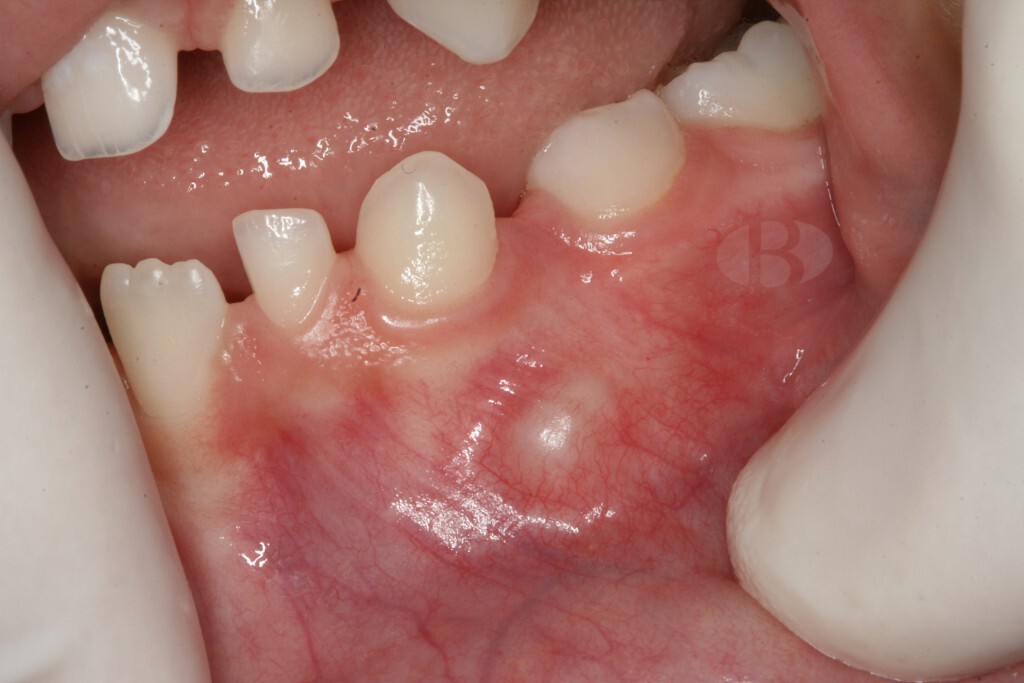

When you hear the word "tumor," there's a good chance you think of cancer. Fortunately, with an odontoma, that's not the case. While an odontoma is a tumor, it's a benign one and not uncommon. That alone is great news! However, odontomas usually require surgical removal. They're made up of dental tissue that resembles abnormal teeth or calcified mass that invade the jaw around your teeth and could affect how your teeth develop. Fortunately, treatment is pretty straightforward and the road to a tumor-free life is one frequently traveled.

Diagnosis and Symptoms

Since odontomas grow internally around your teeth, an X-ray from your dentist is necessary to identify them, notes the AAPD. The shape will indicate to your dentist whether it's compound or complex. While they are asymptomatic, the West Indian Medical Journal Review notes your odontoma could cause:

Swelling

Nearly 80% of those affected by odontomas, though, have teeth that haven't erupted yet. Plus, since they're noncancerous, they rarely grow back after removal.